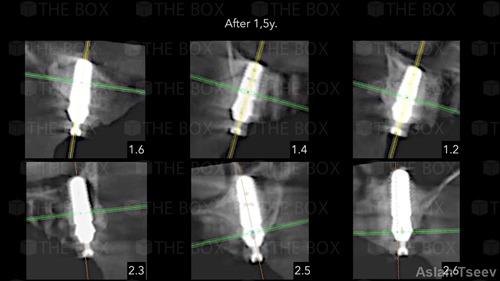

Infra bony defect one wall defect follow up 18 months show regeneration of buccal bone and interdental defect utilizing allograft bone substitute